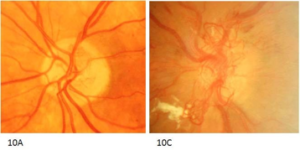

临床上,将眼底的新生血管分为视盘新生血管和视网膜新生血管两种类型。

A. 视盘新生血管

视盘表面或距视盘边缘一个视盘直径范围内的视网膜上的新生血管,以及在此区域前面玻璃体内的新生血管,都被认为是视盘新生血管(NVD)。

B. 视网膜新生血管

位于视网膜表面或延伸到玻璃体内的新生血管被称作视网膜新生血管。

在视盘边缘一个视盘直径(DD)范围内的新生血管定义为视盘新生血管(NVD)的范畴,不定义为视网膜新生血管。

注意:应将新生血管与视网膜内微血管异常相区分:

- 新生血管位于视网膜前,而视网膜内微血管异常则位于视网膜内。

- 新生血管可能会出现在视盘上;视网膜内微血管异常不会出现在视盘上。